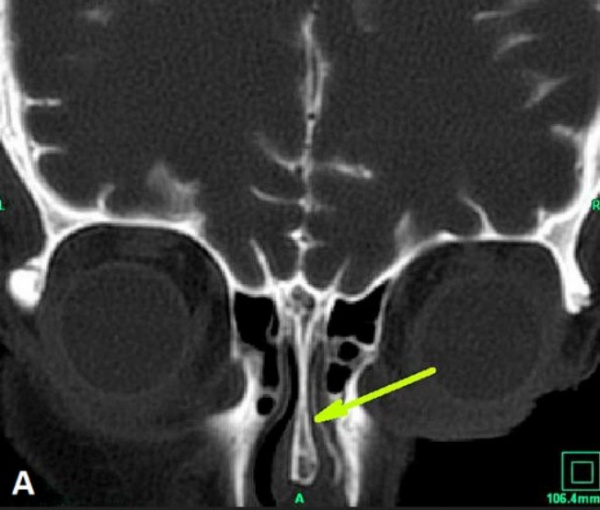

КТ-цистернография. Симптом «ликворной дорожки» — контрастированная СМЖ в правой половине полости носа (стрелка)

· КТ-цистернография. Для непосредственной визуализации ликворных фистул используют КТ-цистернографию с эндолюмбальным введением рентгеноконтрастных препаратов. Контрастное вещество вводится эндолюмбально из расчета 0,15 мл на 1 кг массы тела. Под местной анестезией производят пункцию субарахноидального пространства тонкой иглой в промежутках L3–L4 или L4–L5. Измеряют величину ликворного давления, ЦСЖ отправляют для исследования. В течение следующих 30–40 мин. пациент находится в положении Тренделенбурга, лежа на животе, с согнутым (подбородок прижат к грудине) положением головы. Вначале выполняют боковую сканограмму, по которой планируют необходимое количество сканов во фронтальной проекции.

Послойная фронтальная реконструкция КТ срезов с шагом в 5 мм, как правило, доказательно ликвора за пределы выявляет проникновение субарахноидального контрастированного пространства. Однако следует помнить, что у больных с рецидивирующей ликвореей и скудным характером истечения ЦСЖ данные КТ-цистернографии могут быть отрицательными.

Противопоказания к КТ-цистернографии: 1) окклюзия ликворных путей, препятствующая обследованию в остром периоде тяжёлой ЧМТ пациентов с явлениями отёка-набухания мозга; 2) признаки воспалительного процесса. В настоящем КТ-цистернография в силу своей информативности и адекватности при определении не только состояния костных структур основания черепа, но и анатомо-топографической локализации ликворных фистул может быть отнесена к «золотому стандарту» в диагностике базальных ликворей [4,6] (УД-С).